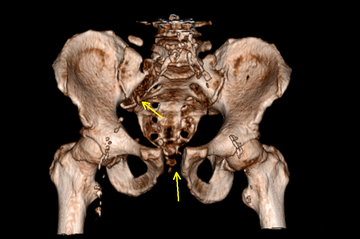

Beckenfrakturen und Frakturen der Hüftgelenkspfanne (Azetabulum) sind komplizierte, teilweise sogar lebensbedrohende Verletzungen. Schwere, instabile Beckenbrüche treten häufig in Verbindung mit Hochenergieverletzungen wie einem Polytrauma auf. Gefäß- und Nervenverletzungen sind in deren Folge nicht selten und können zu einem massiven Blutverlust führen. Die Erstversorgung hängt von der Schwere der Fraktur und der Begleitverletzungen ab. Bei schweren Verletzungen ist zunächst eine Stabilisierung mit einer Beckenzwinge oder einem Fixateur externe notwendig, um andere Verletzungsfolgen primär zu behandeln.

Zur weiterführenden Diagnostik einer Beckenverletzung steht uns modernste radiologische Bildgebung mit 3D-Rekonstruktion zur Verfügung. Auch intraoperativ ist eine 3D-Bildgebung bei laufender Operation möglich. Zur Therapie von vorderen und hinteren Beckenring-Frakturen favorisieren wir Platten-Osteosynthesen offener Reposition, aber auch minimal-invasive Therapieoptionen und transkutane Verschraubungen.